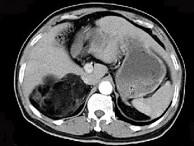

问题 男,59岁,右侧腰背酸痛,CT检查如图所示,应诊断为 ( )

选项 A、右腹膜后脂肪瘤 B、右肾血管平滑肌脂肪瘤 C、右肾上腺转移瘤 D、右肾上腺髓样脂肪瘤 E、右肾上腺腺瘤

答案 D